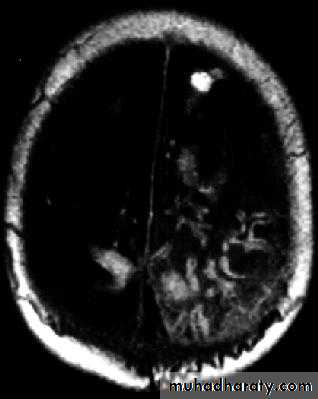

Brain Abscess MRI

• They will show a single (or multiple) space occupying lesion that is well delineated with an enhancing wall, with variable surrounding oedema.

• B. Radiological Investigations:• CT or MRI is the investigation of choice.

• CT Brain is performed with and without contrast.

• MRI is done with gadolinium enhancement.